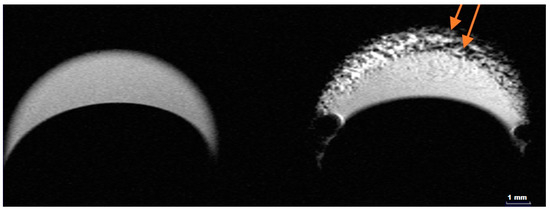

2.4. MRI Contrast Performance of HumAfFt-SPIONs